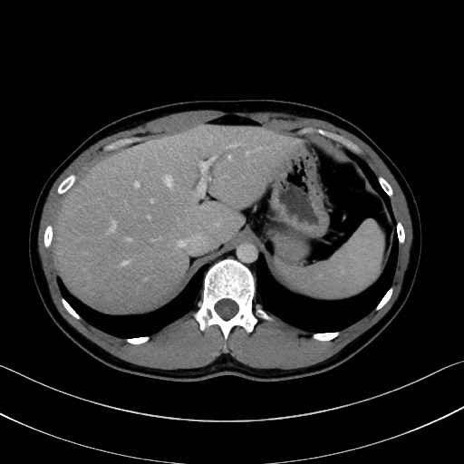

【症例】20歳代 男性 スクリーニング

脾動脈の画像解剖

■起始:典型的には腹腔動脈幹(celiac trunk)から左胃動脈・総肝動脈とともに三分岐し、脾動脈は左後上方へ向かう。

■走行:膵上縁または膵実質背側を蛇行しながら左方へ進み、膵尾部近傍で脾門へ至る。蛇行の程度は個体差が大きい。

■終枝:脾門部で複数の終末枝に分かれ、上極・下極枝や脾門枝群を形成する。胃短動脈群や左胃大網動脈はしばしば脾動脈から分岐する。